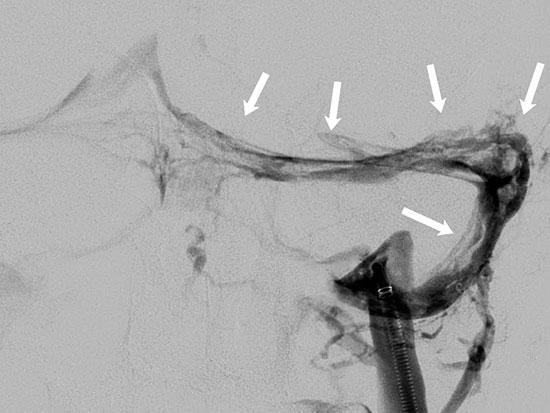

Angiogram images show blood vessels following thrombectomy and treatment with blood thinners.

The arrows indicate scattered blood clots present throughout the venous system, which were diminished in size and extent after treatment.Fisher initially treated Thomas’ blood clots with blood thinners, hydration and pain

medication, which Fisher hoped would dissolve the blood clot and ease Thomas’ symptoms Because Thomas was in the hospital during finals, the School of Health Professions allowed him to take one of his finals on paper rather than on a computer screen, which caused him fewer headaches. However, even after he returned to work part time at the end of December, his headaches were still severe and frequent It was then that he went back to the ER and started to consider surgery to remove the clot.